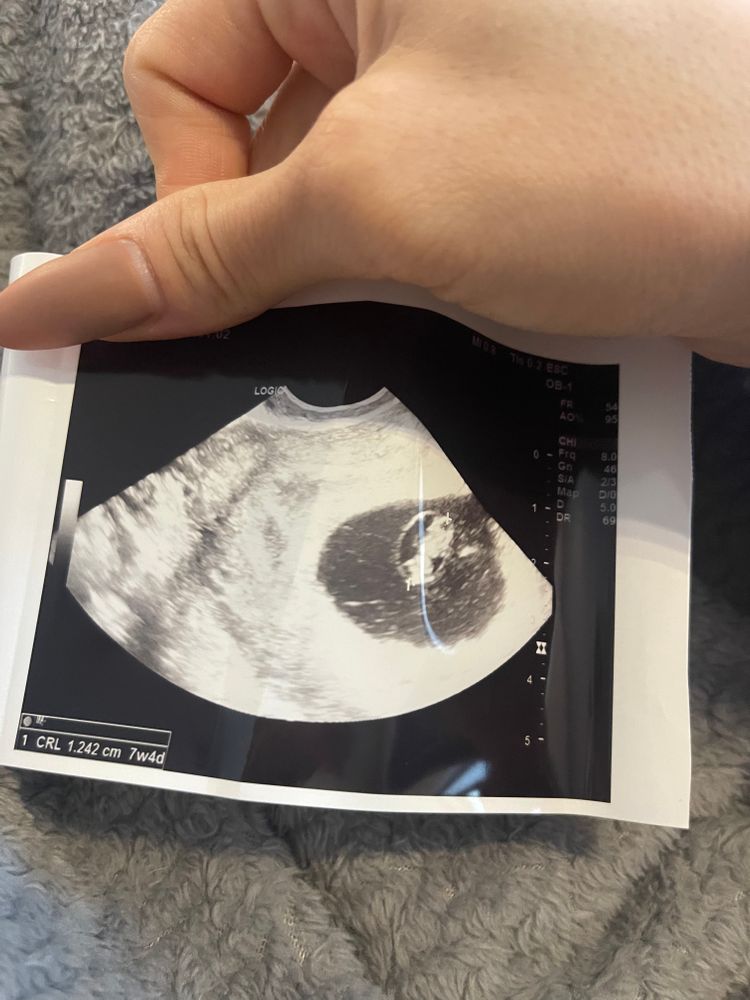

Сердцебиение в одном месте Не видно жм